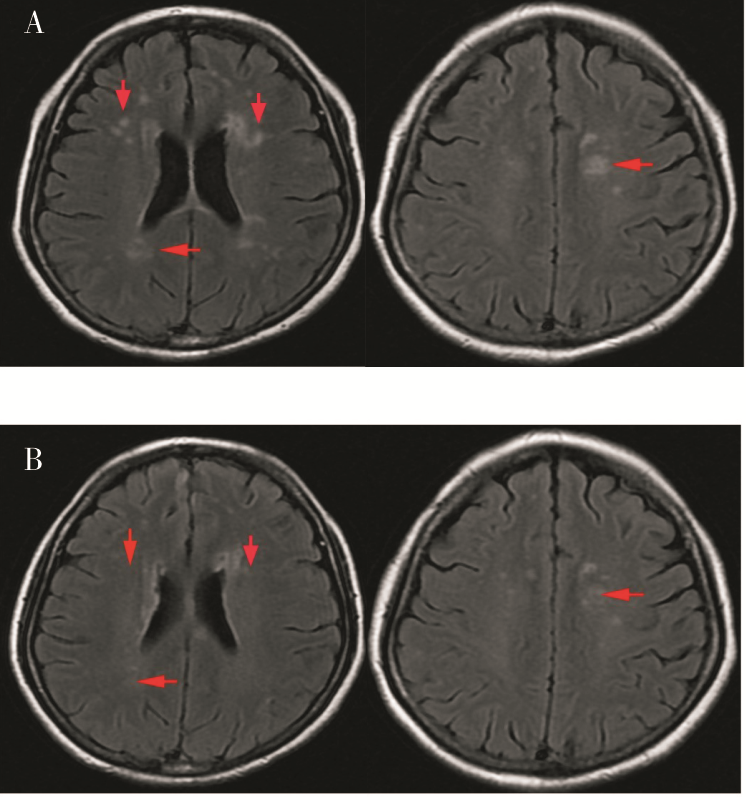

神经精神狼疮是系统性红斑狼疮严重并发症,尤其是累及中枢神经系统时,死亡率明显增加,且目前尚无标准治疗方案。本文报道1例以精神行为异常、谵语为主要表现的神经精神狼疮患者,予以利妥昔单抗序贯贝利木单抗治疗后患者症状缓解,实验室及影像学指标明显改善,为神经精神狼疮的治疗提供了新策略。

CHEN Xue, SUN Mingfang, DAI Huanzi. A case of neuropsychiatric lupus successfully treated with sequential therapy of rituximab and belimumab therapy[J]. Journal of Internal Medicine Concepts & Practice, 2025, 20(04): 316-318.